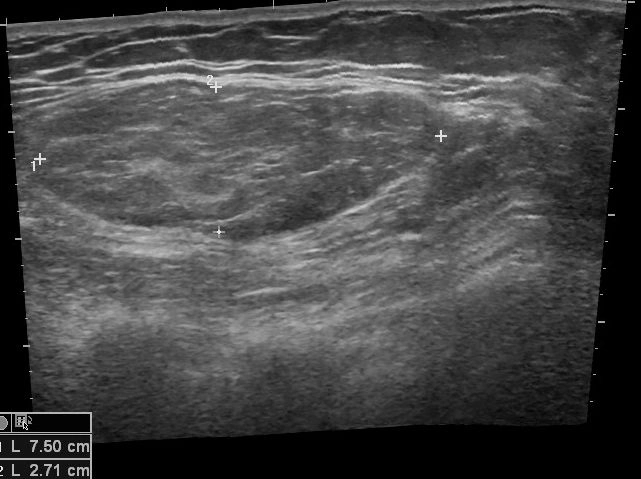

U mỡ thành ngực (Chest Wall Lipomas)